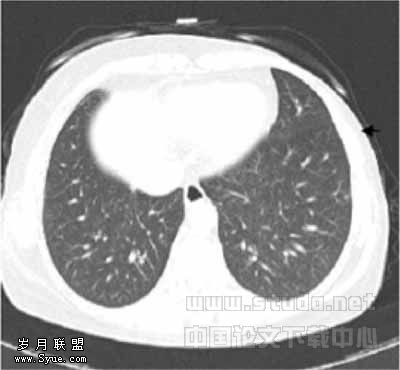

49例图像中,LD1与LD2扫描各有2例图像质量为良好(图1,2),其余均为优秀(图3,4),1例LD扫描图像比SD扫描图像清晰,原因是LD扫描时患者吸气充分而SD扫描时患者吸气不足。

图1,2分别为同一层面的常规剂量与低剂量CT,可见少量伪影,不影响观察肺结节图3,4分别为同一层面的常规剂量与低剂量CT图像,示未见伪影图3示小于5mm肯定肺结节(→?)和模糊肺结节(←?),图4分别显示为肯定(→?)、未见(←?)